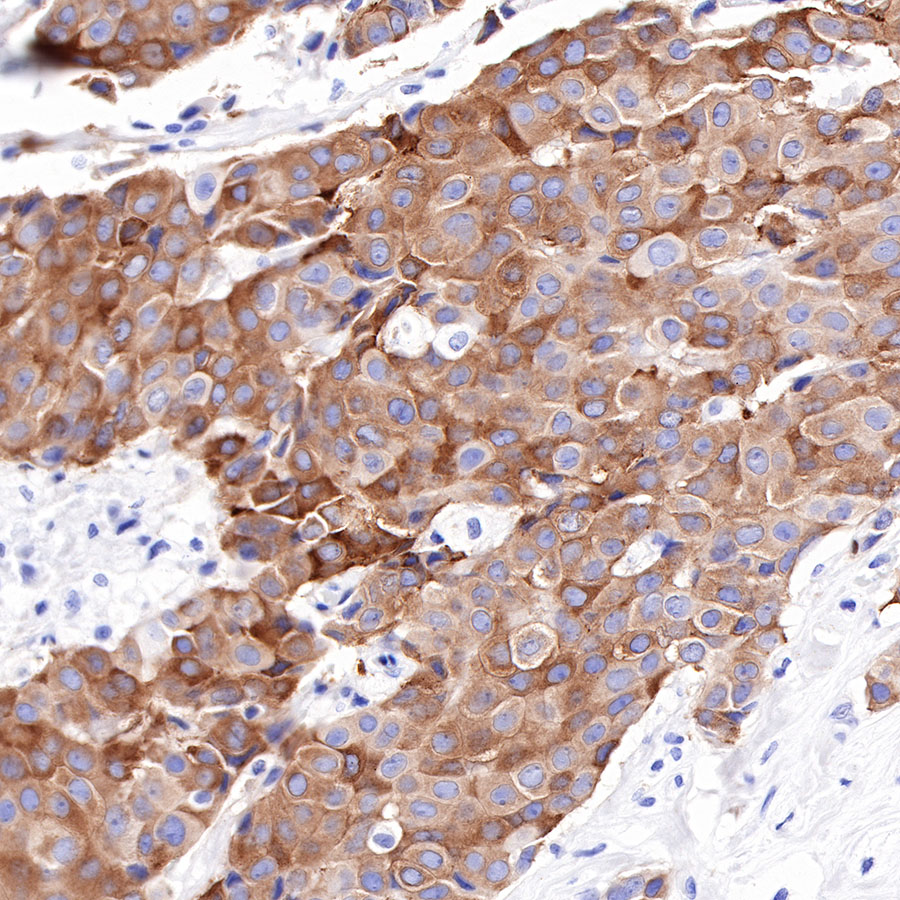

IHC shows positive staining in paraffin-embedded human breast cancer. Anti-Tau antibody was used at 1/2000 dilution, followed by a HRP Polymer for Mouse & Rabbit IgG (ready to use). Counterstained with hematoxylin. Heat mediated antigen retrieval with Tris/EDTA buffer pH9.0 was performed before commencing with IHC staining protocol.